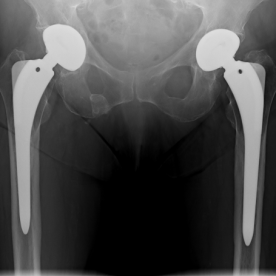

Bei einer Arthrose handelt es sich um eine Knorpelabnutzung in einem Gelenk, wobei unterschiedliche Ausprägungsgrade möglich sind. Je nach Ausprägungsart kommen konservative (Entzündungshemmende Medikamente, physikalische Therapie, orthopädische Hilfen) oder operative Verfahren (arthroskopische Spülung bzw. Gelenktoilette, Knochenumstellungen, Knorpelknochenzelltransplantationen oder prothetische Versorgung) in Frage.